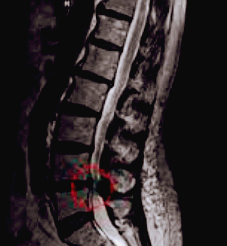

척추 협착증은 CT와 MRI 촬영 등을 통해서 척추관 크기와 주변 관절과 인대 그리고 추간판의 상태를 알아보고 진단을 하게 됩니다. 근전도 검사와 신경전도 검사 등도 같이 하기도 합니다.